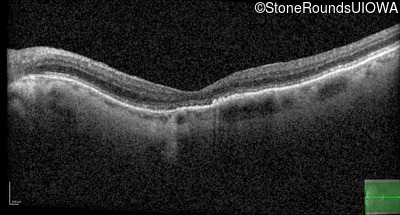

The clinical features favoring the diagnosis of RP1L1-associated occult macular dystrophy include: reduced acuity with a near-normal ophthalmoscopic appearance, a history of normal acuity in childhood; and, a "moth-eaten" appearance of the macular ellipsoid zone on OCT.

This 70 year old woman first noticed some reduction in visual acuity in both eyes at age 45. Her visual acuity had been previously normal.